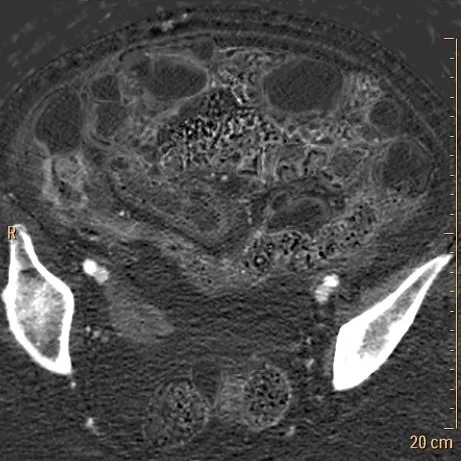

Conventional CT: Note pnematosis in the dilate loop anteriorly.